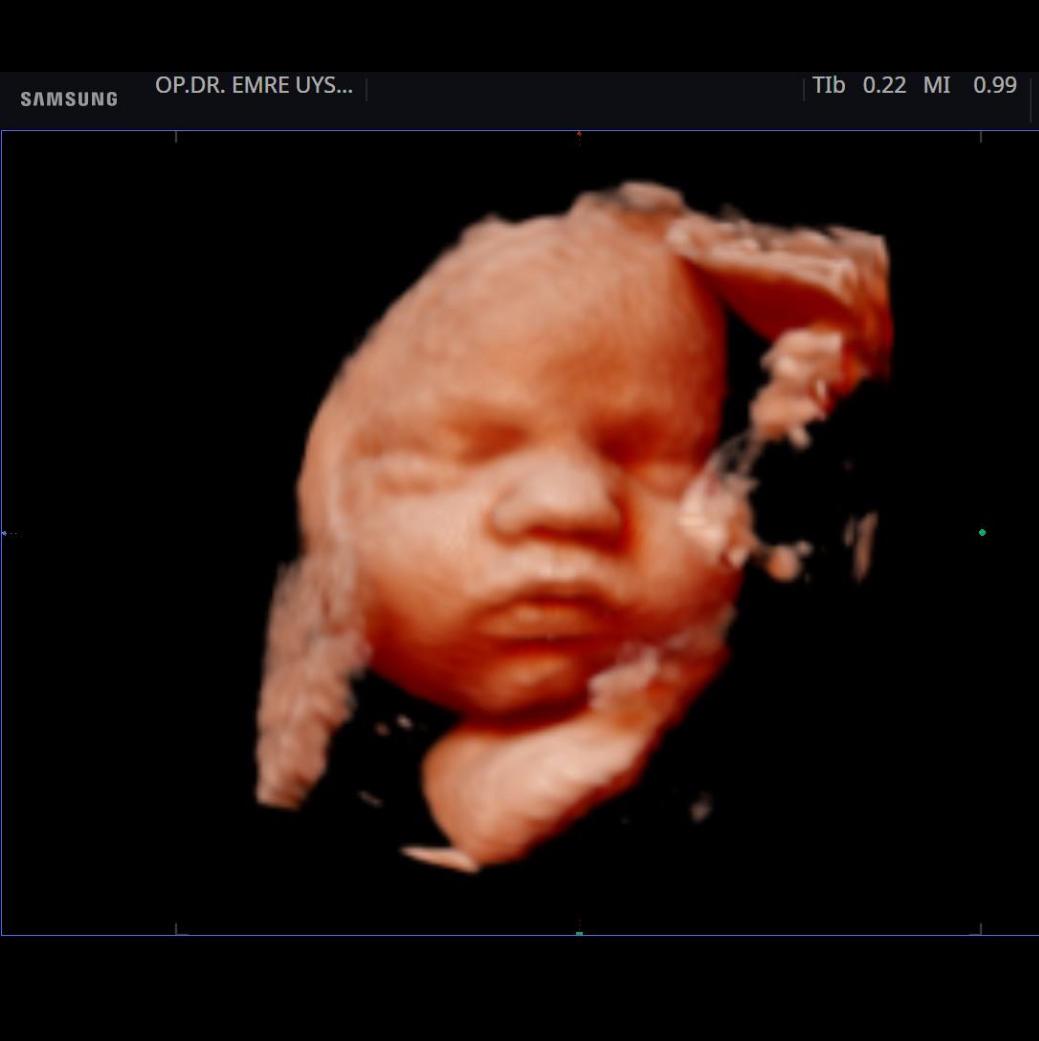

Her kadının hayatında önemli dönüm noktaları vardır. Hiç şüphesizki hamilelik süreci ve doğum bunlardan en kıymetlisidir. Biz de bu değerin farkındayız ve 15 yılı aşan tecrübemiz ile minik mucizenize sağlıkla kavuşma yolculuğunda sizin yanınızdayız. 4d ultrason ile bebeğinizin sağlığını yakından takip ederken, klinik takibimiz ile de süreci eğlenceli ve sağlıklı bir şekilde geçirmeniz için elimizden gelenin en iyisini yapıyor olacağız. Yaşasın Hamilesiniz!